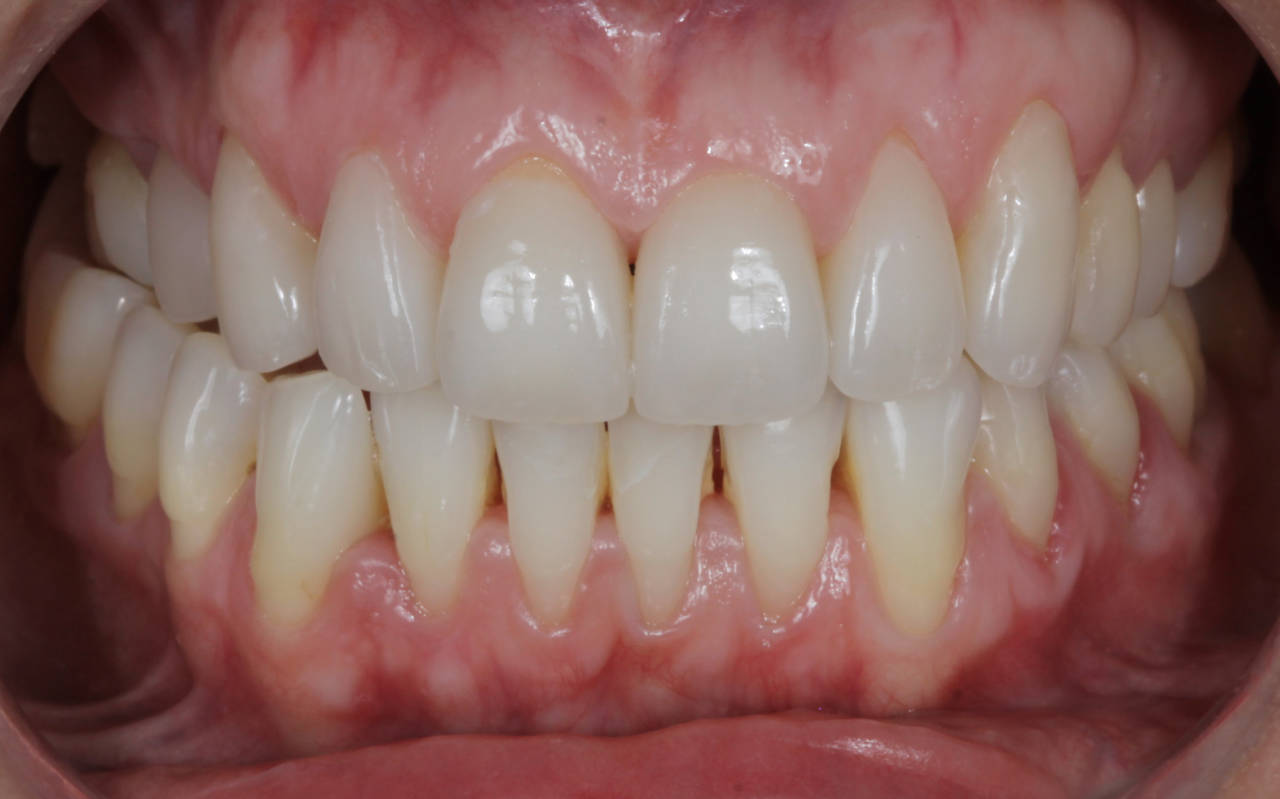

A harmonização do sorriso fez toda a diferença nes